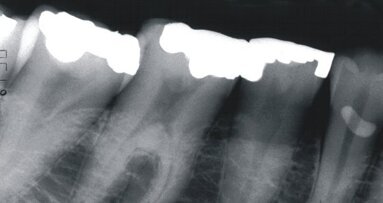

Un homme de 72 ans s'est récemment présenté à notre clinique. Conformément à la plainte majeure du patient, un examen bucco-dentaire et maxillo-facial complet, y compris RX de toute la bouche, a révélé, entre autres, deux implants endo-osseux fracturés, 13 et 12 (Fig. 1).

Ces implants (3,3 mm x 15 mm) ont été placés et mis en charge en 2003. Les implants ont été placés selon le protocole, en utilisant un gabarit chirurgical consistant en deux cylindres de guidage.